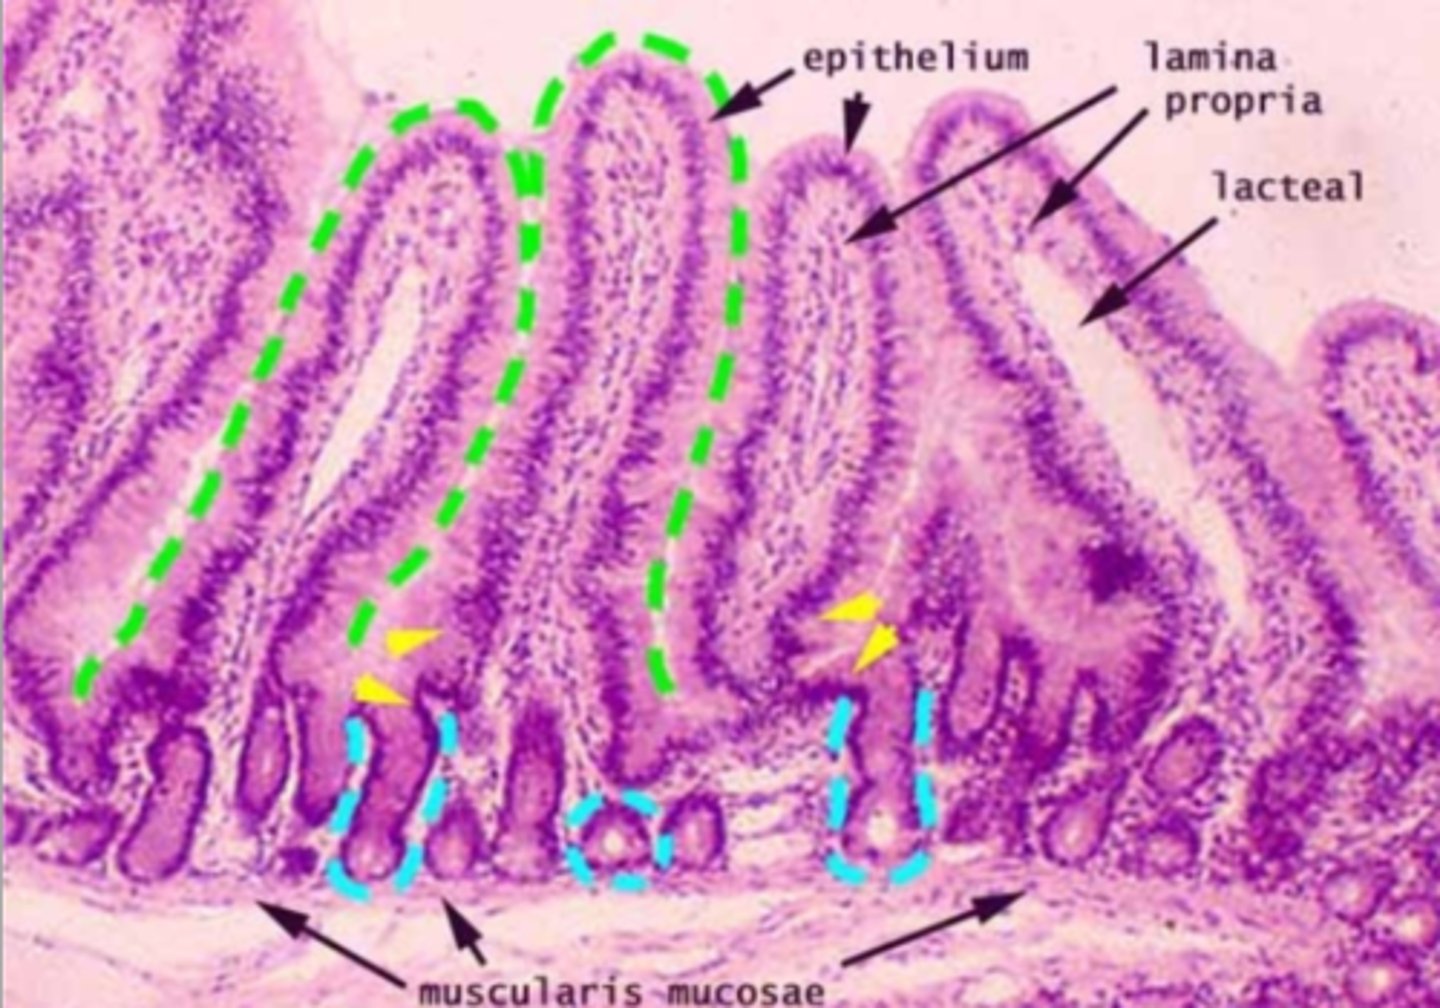

jejunum

What is this?

Jejunum has no Brunner's gland or malt tissue

duodenum and ileum vs jejunum